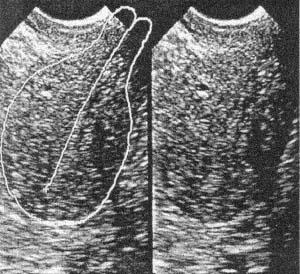

Рис. 19 а, б. Ригидность шеечно-перешеечного отдела. Наполнение мочевого пузыря не устраняет передний перегиб матки, шейка матки при этом отклоняется кзади. Условия для ПЭ ухудшаются.

Наполнение мочевого пузыря не приводит к разгибанию матки при ригидности шеечно-перешеечной области. В этом случае тело матки отклоняется кзади вместе с шейкой, в результате чего изменяется угол между шейкой и влагалищем. Угол между телом матки и шейкой не меняется, что еще более ухудшает условия для ПЭ (рис. 19 а, б). Наложение пулевых щипцов на шейку матки в этом случае также малоэффективно.